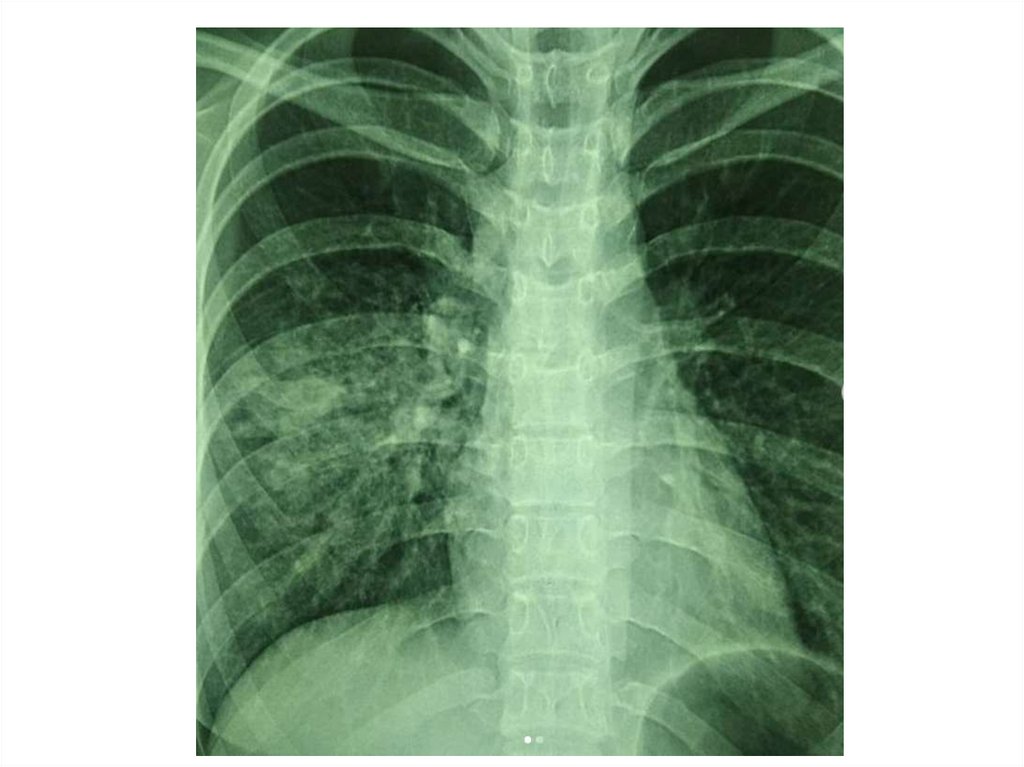

Назовите

• Вид исследования

• Область исследования

• Патологию